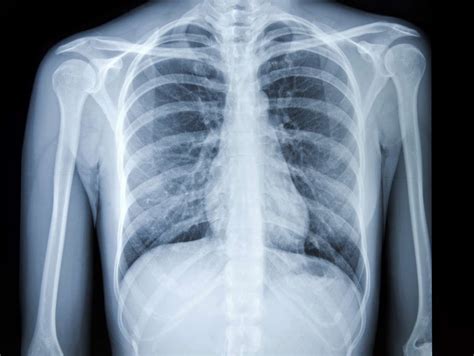

Understanding the importance of a sternum X ray is crucial for anyone involved in medical diagnostics or those who may need to undergo this procedure. A sternum X ray is a diagnostic imaging technique used to visualize the sternum, or breastbone, and the surrounding structures. This procedure is essential for detecting various conditions, including fractures, infections, and tumors. This blog post will delve into the details of a sternum X ray, its indications, preparation, procedure, and interpretation of results.

A sternum X ray is a type of radiographic imaging that uses X-rays to produce images of the sternum and adjacent structures. The sternum is a flat bone located in the center of the chest, which connects to the ribs and forms part of the thoracic cage. This imaging technique is non-invasive and provides valuable information about the bone’s structure and any potential abnormalities.

Interpretation of Sternum X Ray Results

Interpreting the results of a sternum X ray requires the expertise of a radiologist. The images are reviewed for various abnormalities, including:

• Fractures: Visible breaks or cracks in the sternum.

• Infections: Signs of bone destruction or inflammation.

• Tumors: Abnormal growths or masses within the bone.

• Dislocations: Misalignment of the sternum or adjacent structures.

If any abnormalities are detected, further diagnostic tests or treatments may be recommended based on the findings.

Common Findings in a Sternum X Ray

Several common findings can be identified through a sternum X ray. These include:

• Normal Anatomy: A clear view of the sternum and surrounding structures without any abnormalities.

• Fractures: Visible breaks in the bone, which may appear as lines or gaps.

• Osteomyelitis: Signs of infection, such as bone destruction or inflammation.

These findings help healthcare providers determine the appropriate course of treatment.